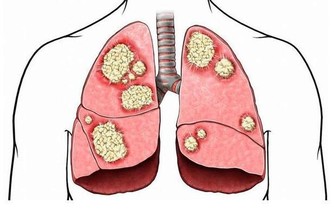

因而角膜會逐漸變尖,最終形成圓錐角膜,圓錐角膜的後果是使視力永遠喪失。

實行了LASIK後所產生的圓錐角膜目前在醫學上被認為是絕症,最後只能用角膜移植來解決問題!